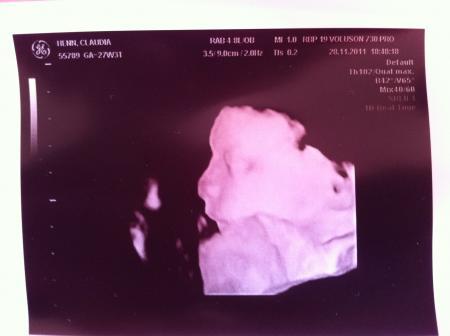

Hallo ihr lieben, endlich konte ich gestern meine kleine Nudel auch mal in 3D betrachten :), nur leider hat sie ihre Nase gegen mein Mutterkuchen gedrückt, so das wir erstmal Schwierigkeiten hatten ein schönes Foto von ihr zu bekommen. Dafür habe ich jetzt ganz viele süße Fotos von meiner kleinen mit plattgedrückter Nase Ansonsten ist alles super, ihr gehts gut und wiegt jetzt 1098g bei ca. 35cm

Bild zu